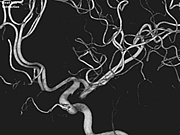

手首や足からカテーテルを通して、心臓を栄養している血管(冠動脈といいます)を造影して、細くなったところを探していきます。

右冠動脈

左冠動脈